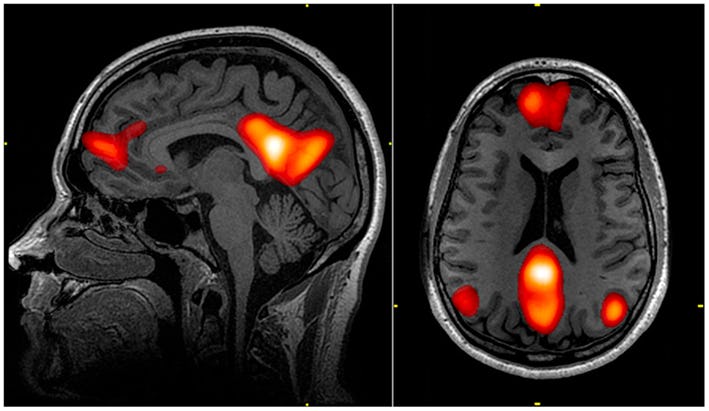

Luckily, a new study brings us one step closer to cracking consciousness once and for all. Researchers have finally provided convincing proof that a relationship between two brain networks — the default mode network, or DMN, and the dorsal attention network, or DAN — may be fundamental to keeping us conscious.

The DMN is a group of brain regions that are active when the brain is at rest; it tends to have lower activity levels when an individual is engaged in a specific mental exercise. While the actual function of the DMN has yet to be determined, it’s thought to have a hand in cognitive processes such as self-reflection, forming autobiographical memories, and playing out potential future events. It is at play when thoughts stream through our mind as we gaze out of a window, or reflect on past memories.

During cognitive tasks that require externally-focused attention, the DMN shuts down, and the DAN comes alive. Their relationship is a reciprocal but competing one; in science, this is referred to as an “anti-correlated” relationship. When one is active, the other is not; like a seesaw in your brain.

Huang and his colleagues used functional magnetic resonance imaging (fMRI) to scan the brains of 98 human participants who were in varying states of consciousness or unresponsiveness. Some patients were rendered unresponsive using anesthetic agents, such as propofol and ketamine. Others suffered from neuropathological conditions that caused disorders of consciousness, such as unresponsive wakefulness syndrome (UWS), also known as a vegetative state.